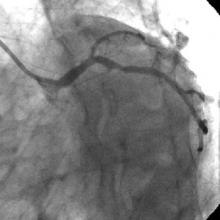

3) LAD: Ostial CTO ( Figure 2) with collaterals from RCA and LCX (Figure 3).

The left system was engaged with XB 3.5 guiding catheter through the femoral route. With the help of a 1.1x1.5mm CTO balloon, we directed a Shinobi guidewire towards the ostial LAD lesion (Figure 4). After making sure that the guidewire was pointing towards the CTO with its tip at the CTO lesion, we used the torquer to gently twirl the guidewire without forcing or overly manipulating it and allowed the guidewire to find its own way through the CTO by patiently twirling it at the lesion site. Within a few minutes, the guidewire jumped through the CTO lesion (Figure 5) and then through the lesion with the help of the CTO balloon (Figure 6). The path was first confirmed by engaging the RCA from the radial approach and injecting dye into the RCA (Figure 7). The CTO was then predilated with a 2.0x30mm Sapphire balloon (Figure 8 and Figure 9) and stented it with a 3.0x36mm DES (Figure 10 and Figure 11). Later the RCA was engaged with a JR 3.5 guiding catheter. A Cougar guidewire crossed the RCA lesion that was directly stented with a 3.0x13mm BMS (Figure 12 and Figure 13).